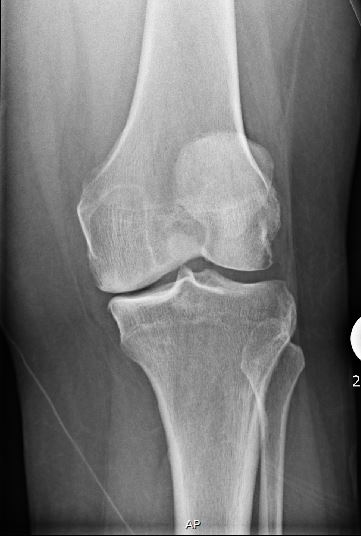

There is much debate as to whether a person should go with a partial knee replacement versus a total knee replacement, considerations to remember are definitely the age at which you are going through with the surgery, the activity level at which you operate, and the level of arthritis you are experiencing. There are advantages and disadvantages to choosing the partial knee versus the total knee replacement, the biggest being that the partial knee allows the knee to feel more normal compared to it feeling so robotic in a total knee. There are 3 types of partial knee surgeries you could accept there is the unicompartmental knee system, the bicompartmental knee system and finally the tricompartmental knee system. The partial knee system is meant to be able to save the ACL and the PCL, this keeps the knee from feeling so robotic. The entire knee is not going to be covered by metal, the metal will encase the bone with plastic spacers in between. The plastic is cemented to the bone with bone cement to ensure that the new knee does not fall away.